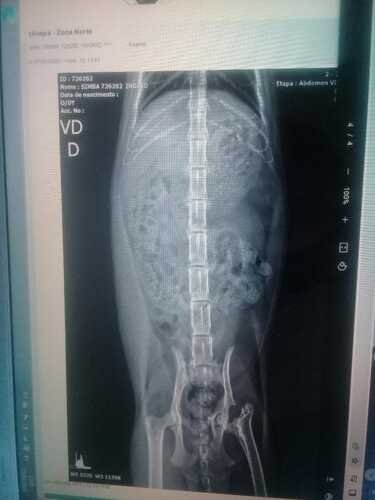

Na queda a Simba abriu o céu da boca, quebrou o fêmur esquerdo e a pata direita. No mesmo dia fomos ao veterinário público que fica localizado na Casa verde Alta na Z/N, ficamos 3 dias indo para o hospital tomar medicações e fazendo exames.

O hospital público oferece a cirurgia apenas do fêmur, não disseram motivo, mas eles não fazem o da pata da frente, fui orientada realizar primeiro a cirurgia da pata que é mais urgente, pois se o osso colar torto, ela terá problemas futuros nas articulações.